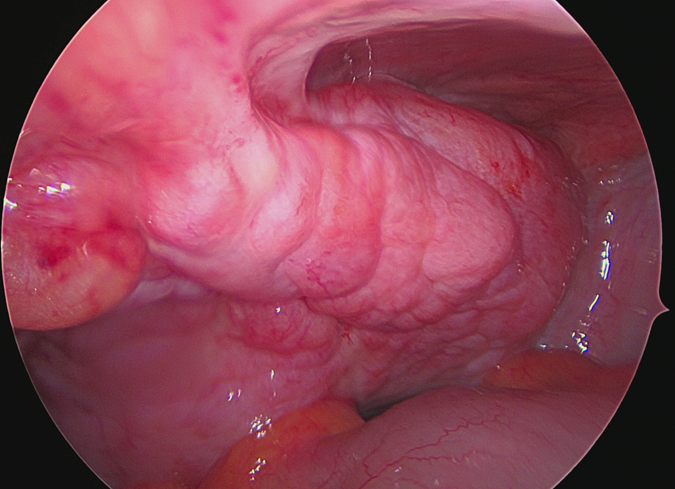

The patient underwent an elective diagnostic cystoscopy and TURBT. The diagnostic cystoscopy (see Figure 1) showed diffuse erythematous and edematous bladder mucosa without any distinct papillary or nodular suspicious lesions. Random cold biopsies and targeted warm biopsies of the erythematous regions were obtained. Retrograde ureteroscopy was not possible; therefore, a retrograde ureterography (see Figure 2) was performed, which showed bilateral distal ureteral stenosis approximately 3 cm proximal to the ureteric orifices, raising suspicion of external compression.

Figure 2: Retrograde ureterography showing bilateral distal ureteral stenosis